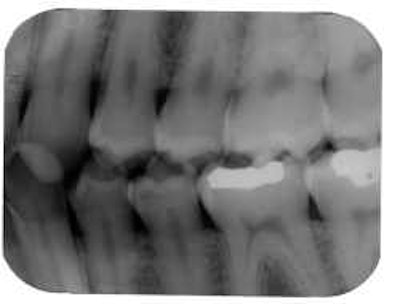

![]() |

| A horizontal angulation error can produce an image with interproximal overlap. |

Use bitewings? Forced to place receptors diagonal to the teeth? Watch out for horizontal angulation errors, which produce a too-wide image with interproximal overlap. The solution is to shoot the x-rays through interproximal surfaces.